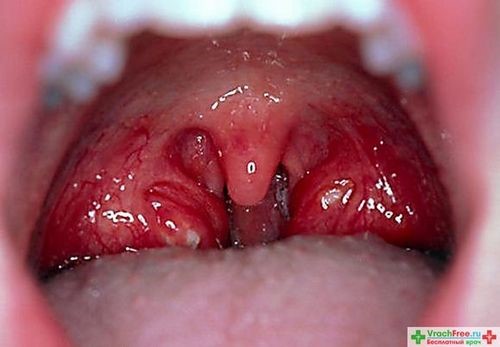

Изменения в миндалинах, выявляемые при визуальном осмотре, а также наличие гнойного отделяемого в лакунах, могут свидетельствовать о хронической рецидивирующей инфекции. Эта проблема не только затрагивает местные ткани, но и может оказывать негативное влияние на весь организм, создавая риск серьезных заболеваний и осложнений. Основной причиной образования гнойников на миндалинах является бактериальная инфекция, среди возбудителей которой можно выделить стрептококки, стафилококки, синегнойную палочку и другие микроорганизмы. При фолликулярной ангине наблюдаются отек и покраснение миндалин, на поверхности которых появляются мелкие белые или желтоватые гнойнички.

При лакунарной ангине на слизистой воспаленных миндалин образуется налет, который скапливается в лакунах. Лакуны представляют собой наружные отверстия каналов (крипт) внутри миндалин, их легко можно увидеть, особенно на увеличенных гландах — это своеобразные «дырки» на их поверхности. Пятна налета белого или желтого цвета могут выходить за пределы лакун и сливаться между собой, покрывая почти всю миндалину. Хронический тонзиллит — это общее заболевание инфекционно-аллергической природы, при котором воспаление локализуется преимущественно в гландах.

Необходимо отметить, что размер гланд не является критерием наличия и тяжести хронического тонзиллита. Миндалины могут быть абсолютно нормального размера, увеличенными или даже атрофированными. При ангине налетам и гнойничкам всегда сопутствуют сильная боль в горле и выраженная интоксикация. Хронический тонзиллит вне обострения характеризуется наличием гнойников на миндалинах без температуры.

Симптомы, сопровождающие образование гнойников на миндалинах, включают в себя сильный болевой синдром и визуальные изменения на гландах и задней стенке горла (покраснение и образование пузырьков с содержание гноя внутри). Заболевание часто сопровождается повышением температуры тела, порой затруднением дыхания и даже нарушением речи, а наличие гнойных пробок обуславливает неприятный запах изо рта.